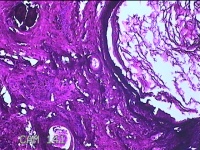

下颌部包块

性别

男

年龄

47岁

临床诊断

皮脂腺囊肿

一般病史

发现下颌部包块3年余,无疼痛及不适。

标本名称

大体所见

灰白暗红色带皮肤结节1.5x1.3x0.8cm一个,表面糜烂,切开结节呈实性,切面灰白粉红色,质软。

图2